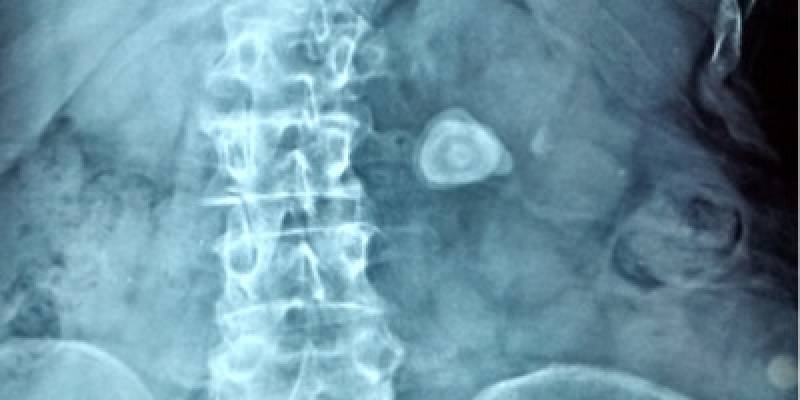

Kidney Stone